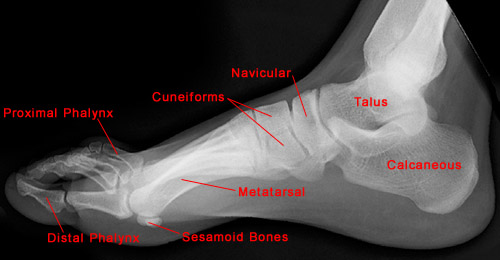

The following images show the normal anatomy of the foot and heel.

• Anatomically, the foot can be divided into three different regions: forefoot, midfoot and hindfoot. The seven tarsal bones of the foot are located within the hindfoot and midfoot, with the hindfoot containing the talus and calcaneus, and the midfoot consisting of the navicular, cuboid, and three cuneiforms. The forefoot contains the metatarsals and phalanges.

• Standard radiographic examination includes AP, lateral and oblique films. Occasionally, a different tangential film may be required for diagnosis.